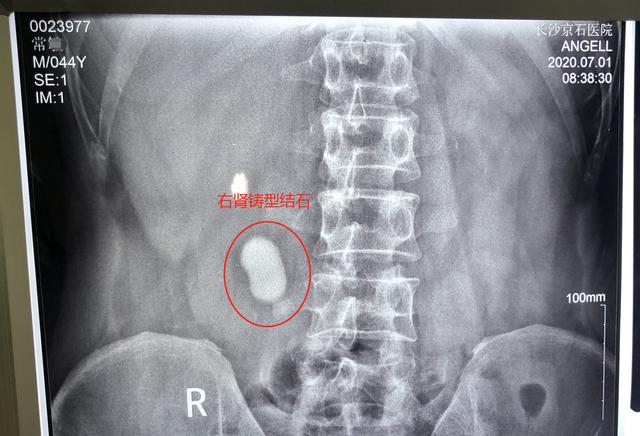

腹平片局部图中白色光团为肾结石

今年6月底,常先生出现右腹部胀痛不适,疼痛加剧时伴有恶心呕吐症状,反复发作。持续数日后,寝食难安的他到当地医院就医,查出右肾铸型结石,且结石直径已有约4公分大。

为寻求专业治疗,常先生多方打听后于7月1日到专治结石的长沙京石结石医院就诊。入院经CT、彩超、尿常规等多项检查,确诊常先生右肾铸型结石并伴有炎症。